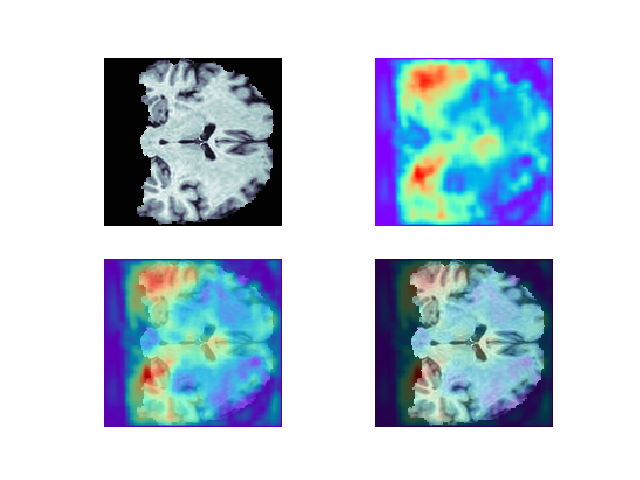

2. 热力图与原始图的叠加

通过以下代码获取热力图,并将其尺寸放缩到与原图一致:

热力图与原图简单叠加:

def easy_show(data, heatmap):

plt.figure()

plt.subplot(221)

plt.axis('off')

plt.imshow(data, cmap='bone')

plt.subplot(222)

plt.imshow(heatmap, cmap='rainbow')

plt.subplot(223)

plt.imshow(heatmap, cmap='rainbow', alpha=0.7)

plt.subplot(224)

plt.imshow(heatmap, cmap='rainbow', alpha=0.3)

plt.savefig(r'E:\study\研究生\笔记\studyNote\others\imgs\tmp.png')

# 使用

heatmap = np.load("CNcam.npy")

img_data = np.load(img_path)

easy_show(img_data[:, 84, :], heatmap[:, 84, :])

图像融合结果: